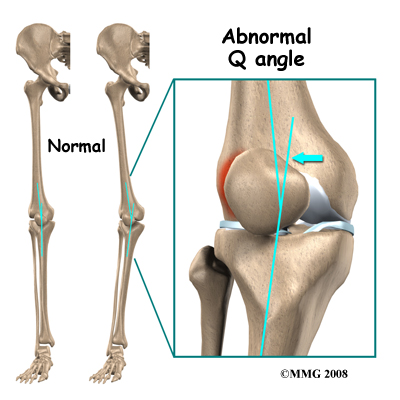

Intrinsic (internal) factors such as age, flexibility, and joint laxity are also important. Malalignment of the foot, ankle, and leg can play a key role in tendonitis. Flat foot position, tracking abnormalities of the patella, rotation of the tibia (called tibial torsion), and a leg length difference can create increased and often uneven load on the quadriceps mechanism.

An increased Q-angle or femoral anteversion are two common types of malalignment that contribute to patellar tendonitis. The Q-angle is the angle formed by the patellar tendon and the axis of pull of the quadriceps muscle. This angle varies between the sexes. It is larger in women compared to men. The normal angle for men or womenis usually less than 15 degrees. Angles more than 15 degrees create more of a pull on the tendon, creating painful inflammation.